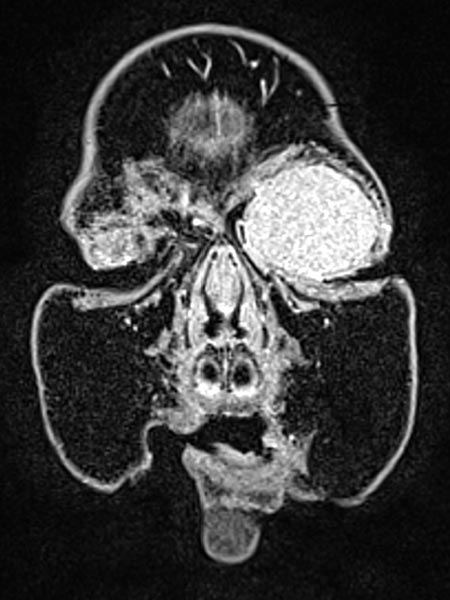

Dynamische, kontrastmittelunterstützte MR-Angiographie des Schädels und der hirnversorgenden Gefäße. In der venösen Phase (C) weiterhin bestehendes starkes, homogenes Enhancement, venöse Drainage über die Vena facialis und Vena jugularis externa links.